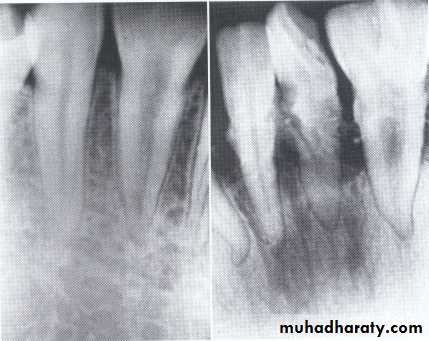

• Fusion of the left mandibular central and lateral incisors (twoindividual roots, two root canals and two joined crowns).

Gemination of right mandibular central incisor has one root, one root canal and a partially bifid dental crown.